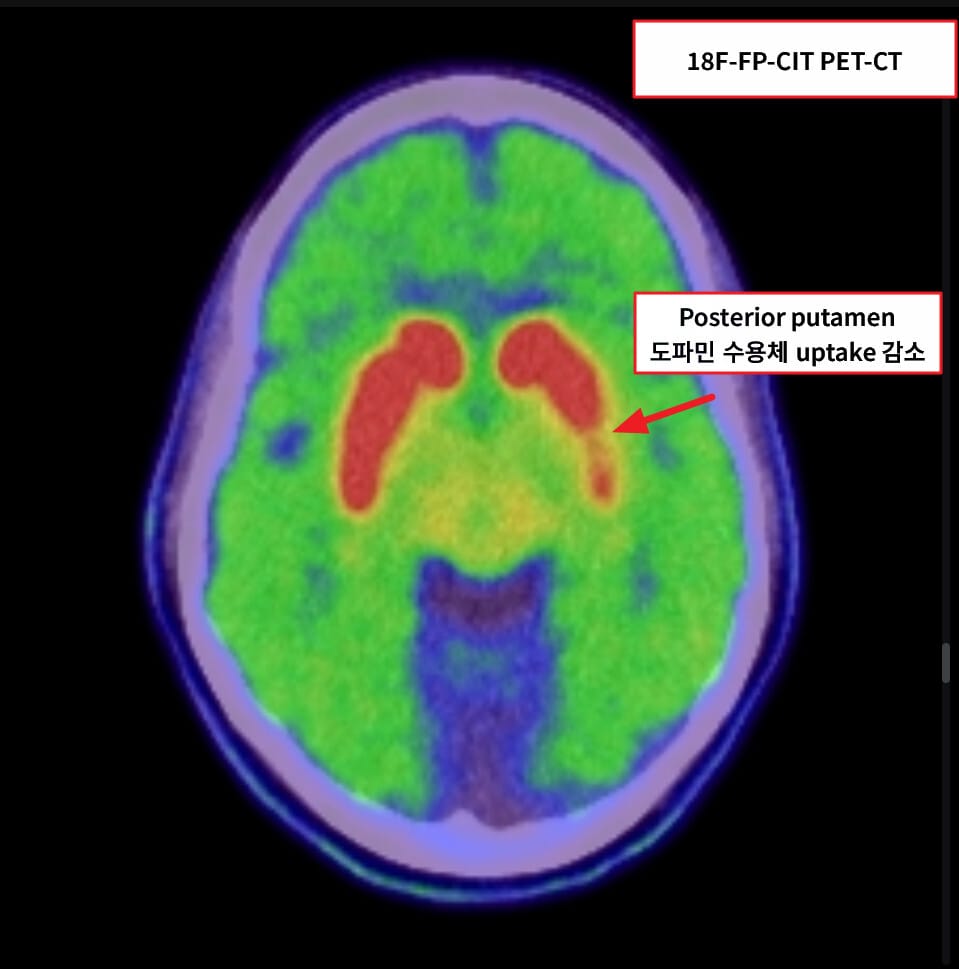

| ✅ 18F-FP-CIT PET-CT : 도파민 수송체 감소 |

| 초기에는 후측 피각(posterior putamen)에서 도파민 수송체 섭취가 감소하며, 점차 전반적 감소로 진행 → 섭취 패턴이 ‘마침표(dot-shaped)’ 또는 ‘단절된 comma’ 형태로 변화 |